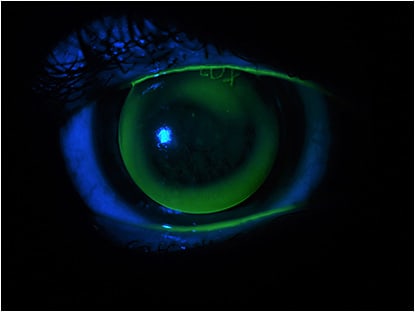

The image above shows a patient who wore the same lens for six years. He experienced extreme difficulty with the fitting and almost gave up lens wear. The image was taken immediately after removing the lens. There is diffuse staining showing keratitis especially around the corneal apex. Either the lens was fit too flat to the cornea or the patient’s keratoconus had progressed. Figure 2 shows the fluorescein pattern of the GP lens that the patient had been wearing.